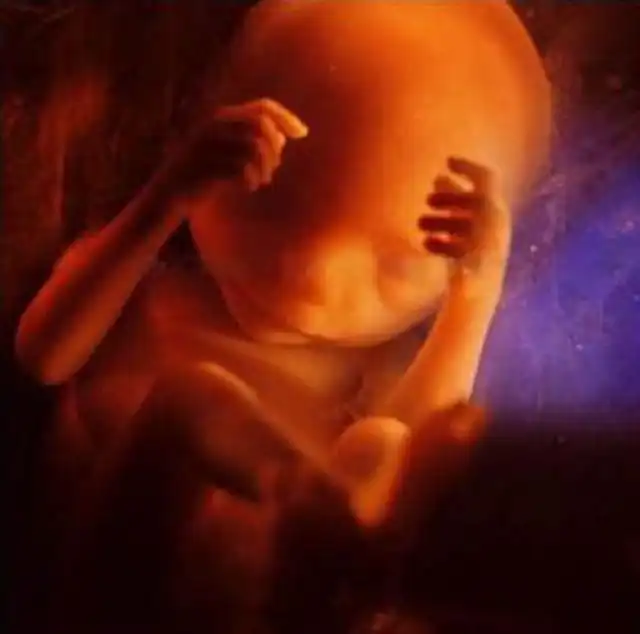

16 недель. Любознательный малыш уже использует свои руки для изучения окрестностей.

Скелет в основном состоит из гибкого стержня и сети кровеносных сосудов, видимой сквозь тонкую кожу.